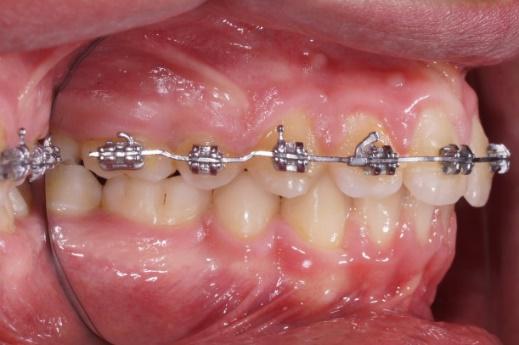

Bagues auto-ligaturantes

Les bagues sont maintenant auto-ligaturantes, il n’existe plus de ligature ( lien bloquant le fil orthodontique dans la rainure de la bague) l’avantage est pratique pour le praticien et moins de gène et une meilleure hygiène pour le patient.